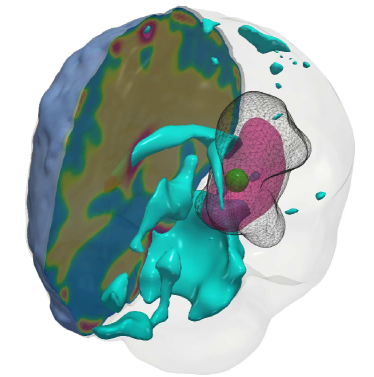

Fig. 4: (a) Description of the visualized brain sub-structures: The figure on the left shows an isometric view of the brain with different tumorous and healthy tissue sub-structures. The figure on the right zooms in on the tumor region and describes each structure. (b, c) Qualitative results for the artificial tumor test-case AT-C1 (a mono-focal, mostly proliferative tumor) with growth parameters ρ=8,κ=0.025formulae-sequencesuperscript𝜌8superscript𝜅0.025\rho^{\star}=8,~{}\kappa^{\star}=0.025. The images show the tumor data (gray wireframe), ground truth tumor initial condition (green volume), reconstructed tumor initial condition (magenta volume), ventricles (cyan volume), and a section of the patient brain geometry. We observe exact reconstruction for smaller tumors with sparsity constraints. The \mathboldL2\mathboldsubscript𝐿2\mathbold{L_{2}} solver fails to obtain the same reconstruction due to its inability to determine the correct reaction coefficient. We refer the reader to Tab. 4 for the quality of final tumor reconstruction.

Fig. 5: Qualitative results for the artificial tumor test-case AT-C2 (a mono-focal tumor that has grown more and is infiltrative) with growth parameters ρ=12,κ=0.05formulae-sequencesuperscript𝜌12superscript𝜅0.05\rho^{\star}=12,~{}\kappa^{\star}=0.05. The images show the tumor data (gray wireframe), ground truth tumor initial condition (green volume), reconstructed tumor initial condition (magenta volume), ventricles (cyan volume), and a section of the patient brain geometry. As with smaller tumors, the \mathboldL2\mathboldsubscript𝐿2\mathbold{L_{2}} solver predicts an initial condition reconstruction that has a large support and lacks localization capabilities. Hence, the solver is unable to determine the reaction coefficient accurately. While sparsity constraints help in localizing the initial condition, an exact initial condition reconstruction is difficult due to the ill-conditioned inverse problem.

Setup. We grow synthetic tumors in the segmentation of a statistical brain atlas [8] MRI scan (an atlas obtain by averaging several MR images). The segmentation labels are gray matter, white matter, and cerebrospinal fluid-filled ventricles (CSF). We use sparse initial conditions to grow the tumor to a significant size resembling clinical observations and invert for all biophysical parameters using the grown tumor at t=1𝑡1t=1 as input data to the solver. For all our test cases, we assume that the tumor grows and diffuses only in white matter. For this test-case, we observe the data everywhere, i.e., cd=0subscript𝑐𝑑0c_{d}=0. We consider the following variations:

(i) AT-C1: medium sized, mono-focal tumor ρ=8superscript𝜌8\rho^{\star}=8 κ=0.025superscript𝜅0.025\kappa^{\star}=0.025

(ii) AT-C2: large sized, mono-focal tumor ρ=12superscript𝜌12\rho^{\star}=12 κ=0.05superscript𝜅0.05\kappa^{\star}=0.05

(iii) AT-C3: multi-focal tumor, nearby seeds ρ=10superscript𝜌10\rho^{\star}=10 κ=0.025superscript𝜅0.025\kappa^{\star}=0.025

(iv) AT-C4: multi-focal tumor, distant seeds ρ=8superscript𝜌8\rho^{\star}=8 κ=0.025superscript𝜅0.025\kappa^{\star}=0.025

We report our quantitative results (performance measures, convergence, and solver timings) in Tab. 4 and visualize the reconstruction to qualitatively assess the performance of our solvers in Fig. 4 - Fig. 7. Each figure shows an isometric view of the patient brain with 3D volumes of the grown tumor data, ground truth, and reconstructed initial condition. We additionally visualize the ventricles and sections of healthy tissue to reveal the heterogeneity of the brain (and hence the tumor).

Observations. We observe that for the medium sized tumor (AT-C1) the reconstruction is nearly perfect for the CS solver while the \mathboldL2\mathboldsubscript𝐿2\mathbold{L_{2}} solver produces a lower performance, particularly in the inversion of the reaction coefficient. This is primarily due to the rich initial conditions produced by the \mathboldL2\mathboldsubscript𝐿2\mathbold{L_{2}} solver which impedes its ability to predict the correct reaction scaling using our method. We note that if the reaction scaling is known beforehand, the \mathboldL2\mathboldsubscript𝐿2\mathbold{L_{2}} solver can potentially have better performance (see [56, 16] for similar synthetic experiments). This problem is magnified for larger tumors (AT-C2 and AT-C3) where the predicted reaction coefficient shows about 66%percent6666\% and 54%percent5454\% relative error in the \mathboldL2\mathboldsubscript𝐿2\mathbold{L_{2}} solver for the two test-cases respectively (as compared to around 15%percent1515\% and 1%percent11\% error with sparsity constraints). The reconstruction in diffusivity also suffers similarly without enforcing sparsity. The final test-case shows a multi-focal tumor with two far apart proliferation sites. While both the solvers produce disjoint initial conditions for the tumor, the CS solver does better in reconstructing the model parameters: 2% versus 37% relative error in diffusivity and 9% versus 50% relative error in reaction coefficient. Both solvers show similar performance in their ability to fit the data (as measured by the relative error in final tumor reconstruction). Hence, our synthetic observations show consistent improvement in target parameter estimation for all test-cases with sparse initial conditions, without sacrificing the final tumor reconstruction quality.